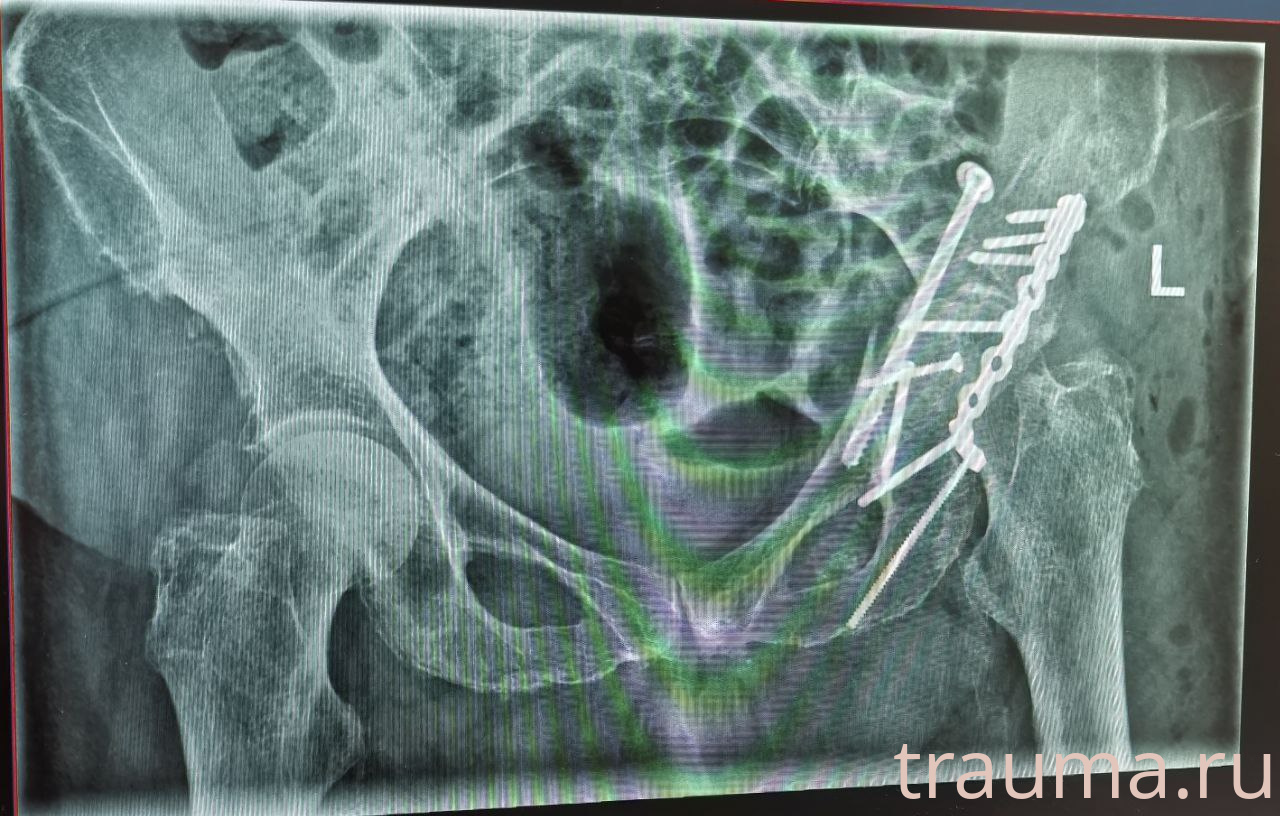

Рентгенограммы

Рентген на дому: по вашему адресу приезжает врач-рентгенолог, травматолог-ортопед с мобильным рентгеновским аппаратом, проводит диагностику травмы или заболевания, делает необходимые рентгенограммы, дает рекомендации по дальнейшему лечению. Получить качественные снимки в домашних условиях возможно благодаря уникальной методике, разработанной МосРентген Центром для института  Склифосовского